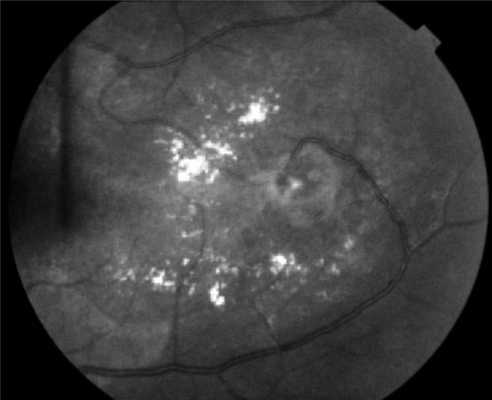

Поражения глаз выявляются примерно у 37% пациентов с VHL-синдромом, среди них только у 14% обнаруживается полная делеция VHL [51, 52]. Приблизительно у 8% пациентов снижена острота зрения [53]. Для лечения ангиомы сетчатки используют лазерную или криотерапию [32, 34, 54]. Недавние исследования [ 55, 56] показали, что при внутривенном введении антагониста сосудистого эндотелиального фактора роста (anti-VEGF) в течение 7 мес размер гемангиобластом не уменьшается (рис. 3). Рисунок 3. Ангиоматоз сетчатки.